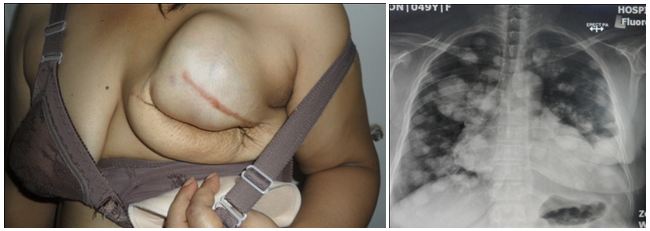

A PET scan was done and the results showed the cancer had spread from the liver to his lung and lymph nodes around his neck.

Take a look at the PET scan done in the TCM university hospital. His cancer is serious. His liver is badly damaged. And the cancer has spread to his lymph nodes and lungs. What is his chance of cure? Can we be honest about it?

After looking at Henry’s PET scan and his blood test results — take note his alpha-fetoprotein was at 275,330 — I frankly told Henry no one on earth can ever “cure” him. He has to be realistic and know that his liver cancer is incurable. If he is able to live a quality life — can eat, can sleep, can move around and no pain — then be grateful and don’t ask for more.